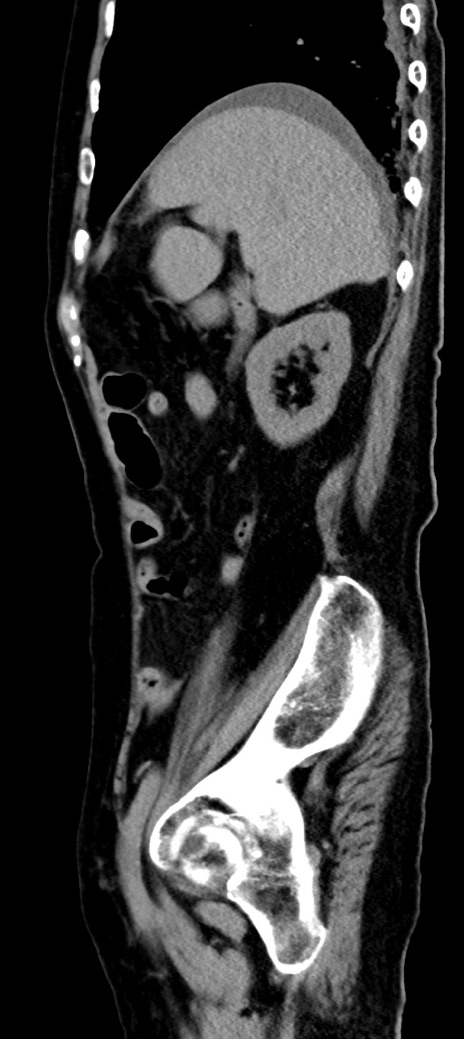

症例40(矢状断像)他院1日前

【症例】90歳代女性

【主訴】腹痛・嘔吐

【現病歴】 食欲低下、嘔吐があり昨日他院受診。肺炎と診断され入院となる。入院後より腹部全体に圧痛あり。胃管留置され経過みていたが、症状持続するため、

当院転院となる。

【既往歴】胸椎圧迫骨折、胆石症

【身体所見】腹部:中央に激痛あり、圧痛あり、反跳痛不明

【データ】WBC 17100、CRP 18.82